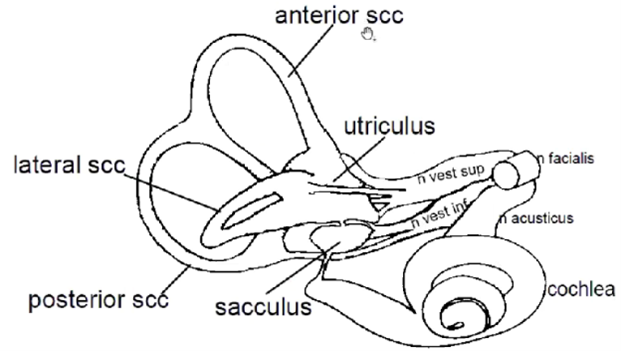

- SCC – semi cirkular canal (båggång)

Vad ansvara de olika delarna för?

- SCC – semi cirkular canal (båggång)

- Anterior (rörelser framåt snett)

- Posterior (rörelser bakåt snett)

- Lateral (huvud fram och tillbaka horisontalt)

- Cochlea ger info till n. acusticus

- Balanssystem består av tre båggångar som ger information till

- övre vestibularisnerv – anterior scc, lateral scc och utriculus

- nedre vestibularisnerv – posterior scc och sacculus

- Ovan tre nerver går ihop till n. vestibulocochlearis och sällskapar sen med n. fascialis

Temporal fraktur kan ge problem med vad med tanke på vilke nerver som löper där?

Balans (vestibulär del), hörsel och muskler i ansikte